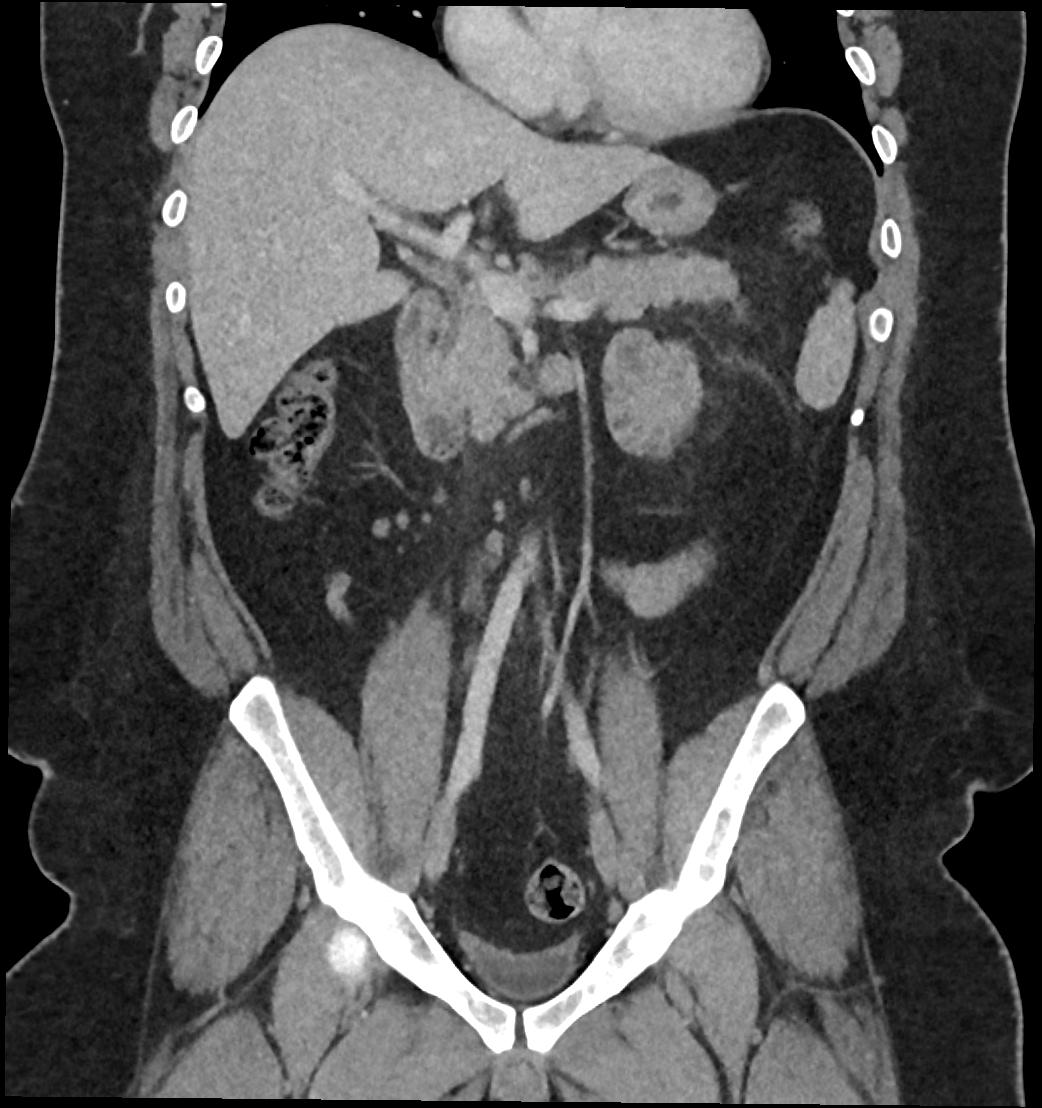

Patient: Padmakumar A. , *1988-04-24, PID: 3000069741773230809

Study Description: CT ABDOMEN

Image Series: Abdomen Cor 3mm [4]

<< Previous | Image 57 of 119 | Next >>